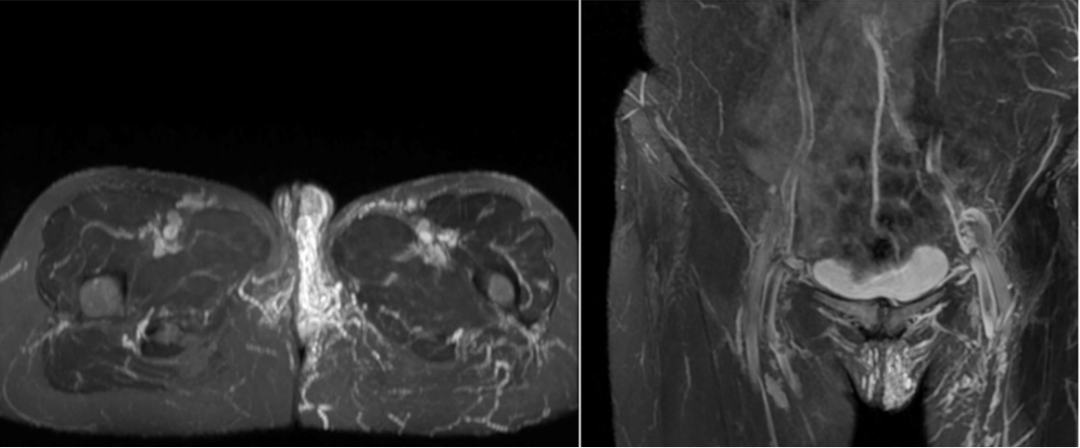

图:PCS患者外阴静脉曲张的MRI表现